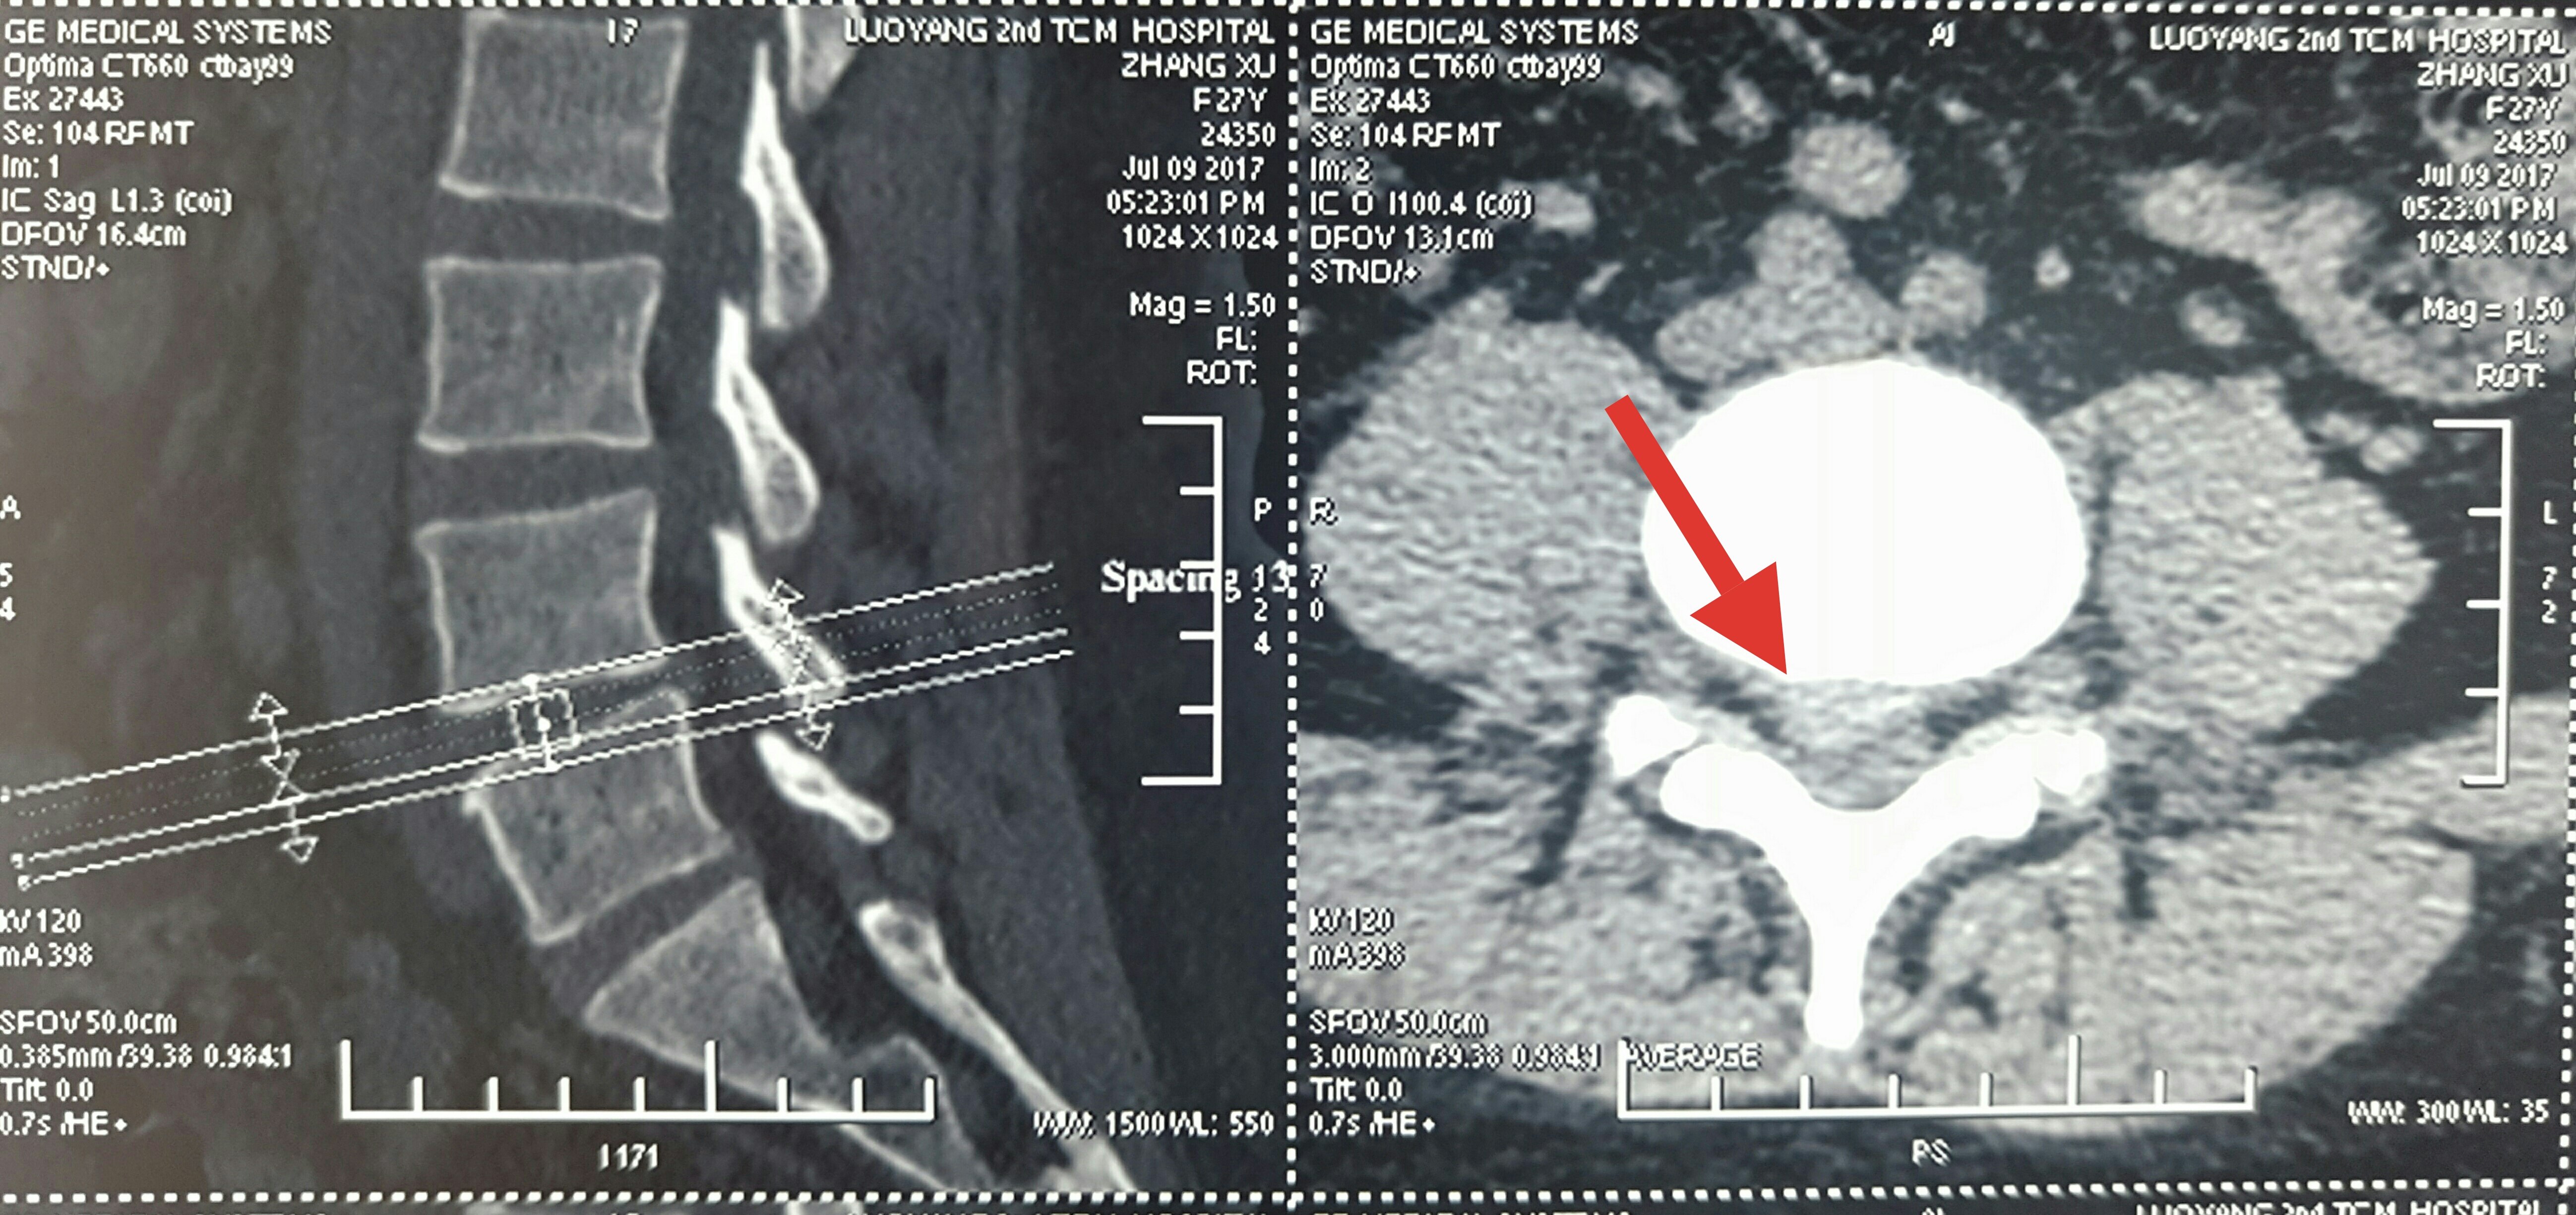

脊柱内镜翻修腰椎间盘突出症胶原酶溶核术后复

5312x3984 - 2972KB - JPEG

脊柱内镜翻修腰椎间盘突出症胶原酶溶核术后复

5310x2870 - 2720KB - JPEG